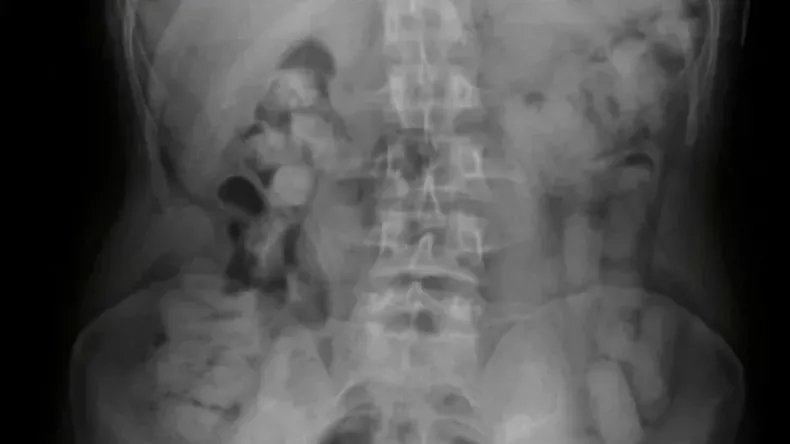

Ante la presunción de delito, se contactó al Juzgado Federal de Tucumán, que autorizó su traslado a un nosocomio local para realizar placas radiográficas.

Los estudios médicos confirmaron cuerpos extraños en los estómagos de los pasajeros, quienes quedaron bajo observación. Tras un día de internación, evacuaron 235 cápsulas con un peso total de 2 kilos 554 gramos de cocaína.